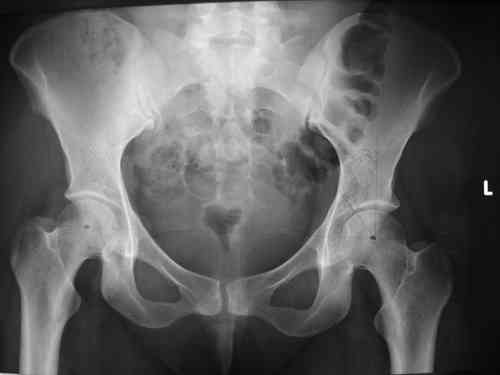

прилагаю пример с такой же давностью травмы, репонировали аппаратом